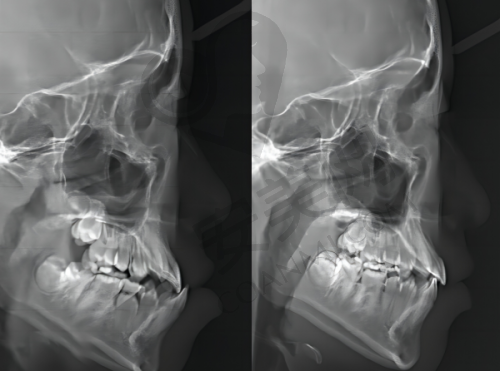

医生团队会运用精良的 3D 数字化美学正畸设计,为患者制定个性化的正畸方案。无论是牙齿不齐、牙齿拥挤还是龅牙、地包天等问题,都能得到有效的解决。在正畸过程中,医生会根据患者的牙齿移动情况及时调整方案,确保正畸成效达到至佳。